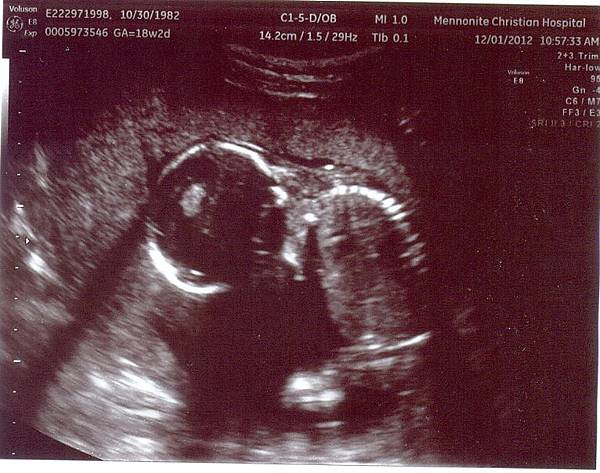

期待好久的超音波終於要來了

蹦米乓竟然跪著頭低低的

天地良心啊~~

我可沒有處罰你跪在那裡啊~~~

為了什麼事如此委屈呢???

不過這個姿勢就像在禱告

看了就覺得好可愛呀

蹦米乓是敬虔的寶寶嗎?

買了兩張超音波

跪著的那張超經典一定要買下來

然後晃一晃蹦米乓又把腳伸直

就像青蛙一樣的兩條腿

照得好清楚呀

這張也把它買下

我說照超音波真的就是要快、狠、準才能找到好的pose

蹦米乓非常乖巧也健康的長大中

看到了胃、大腿骨還有臍帶

門諾的超音波師真的好棒

很有耐心的解釋給我們聽

蹦米乓一直都在握拳

所以看不到手指頭

不過其它的部位都照得很清楚

啊~~~上個月還可以拍全身照

這個月一個畫面已經放不下一個蹦米乓了

要分部位看

至於我們最想知道的性別

因為蹦米乓擋來擋去的所以看不清楚

不過超音波師努力的看了一下說

hmmmm.....這個腿之間凸凸的地方,看來似乎是比較像男生